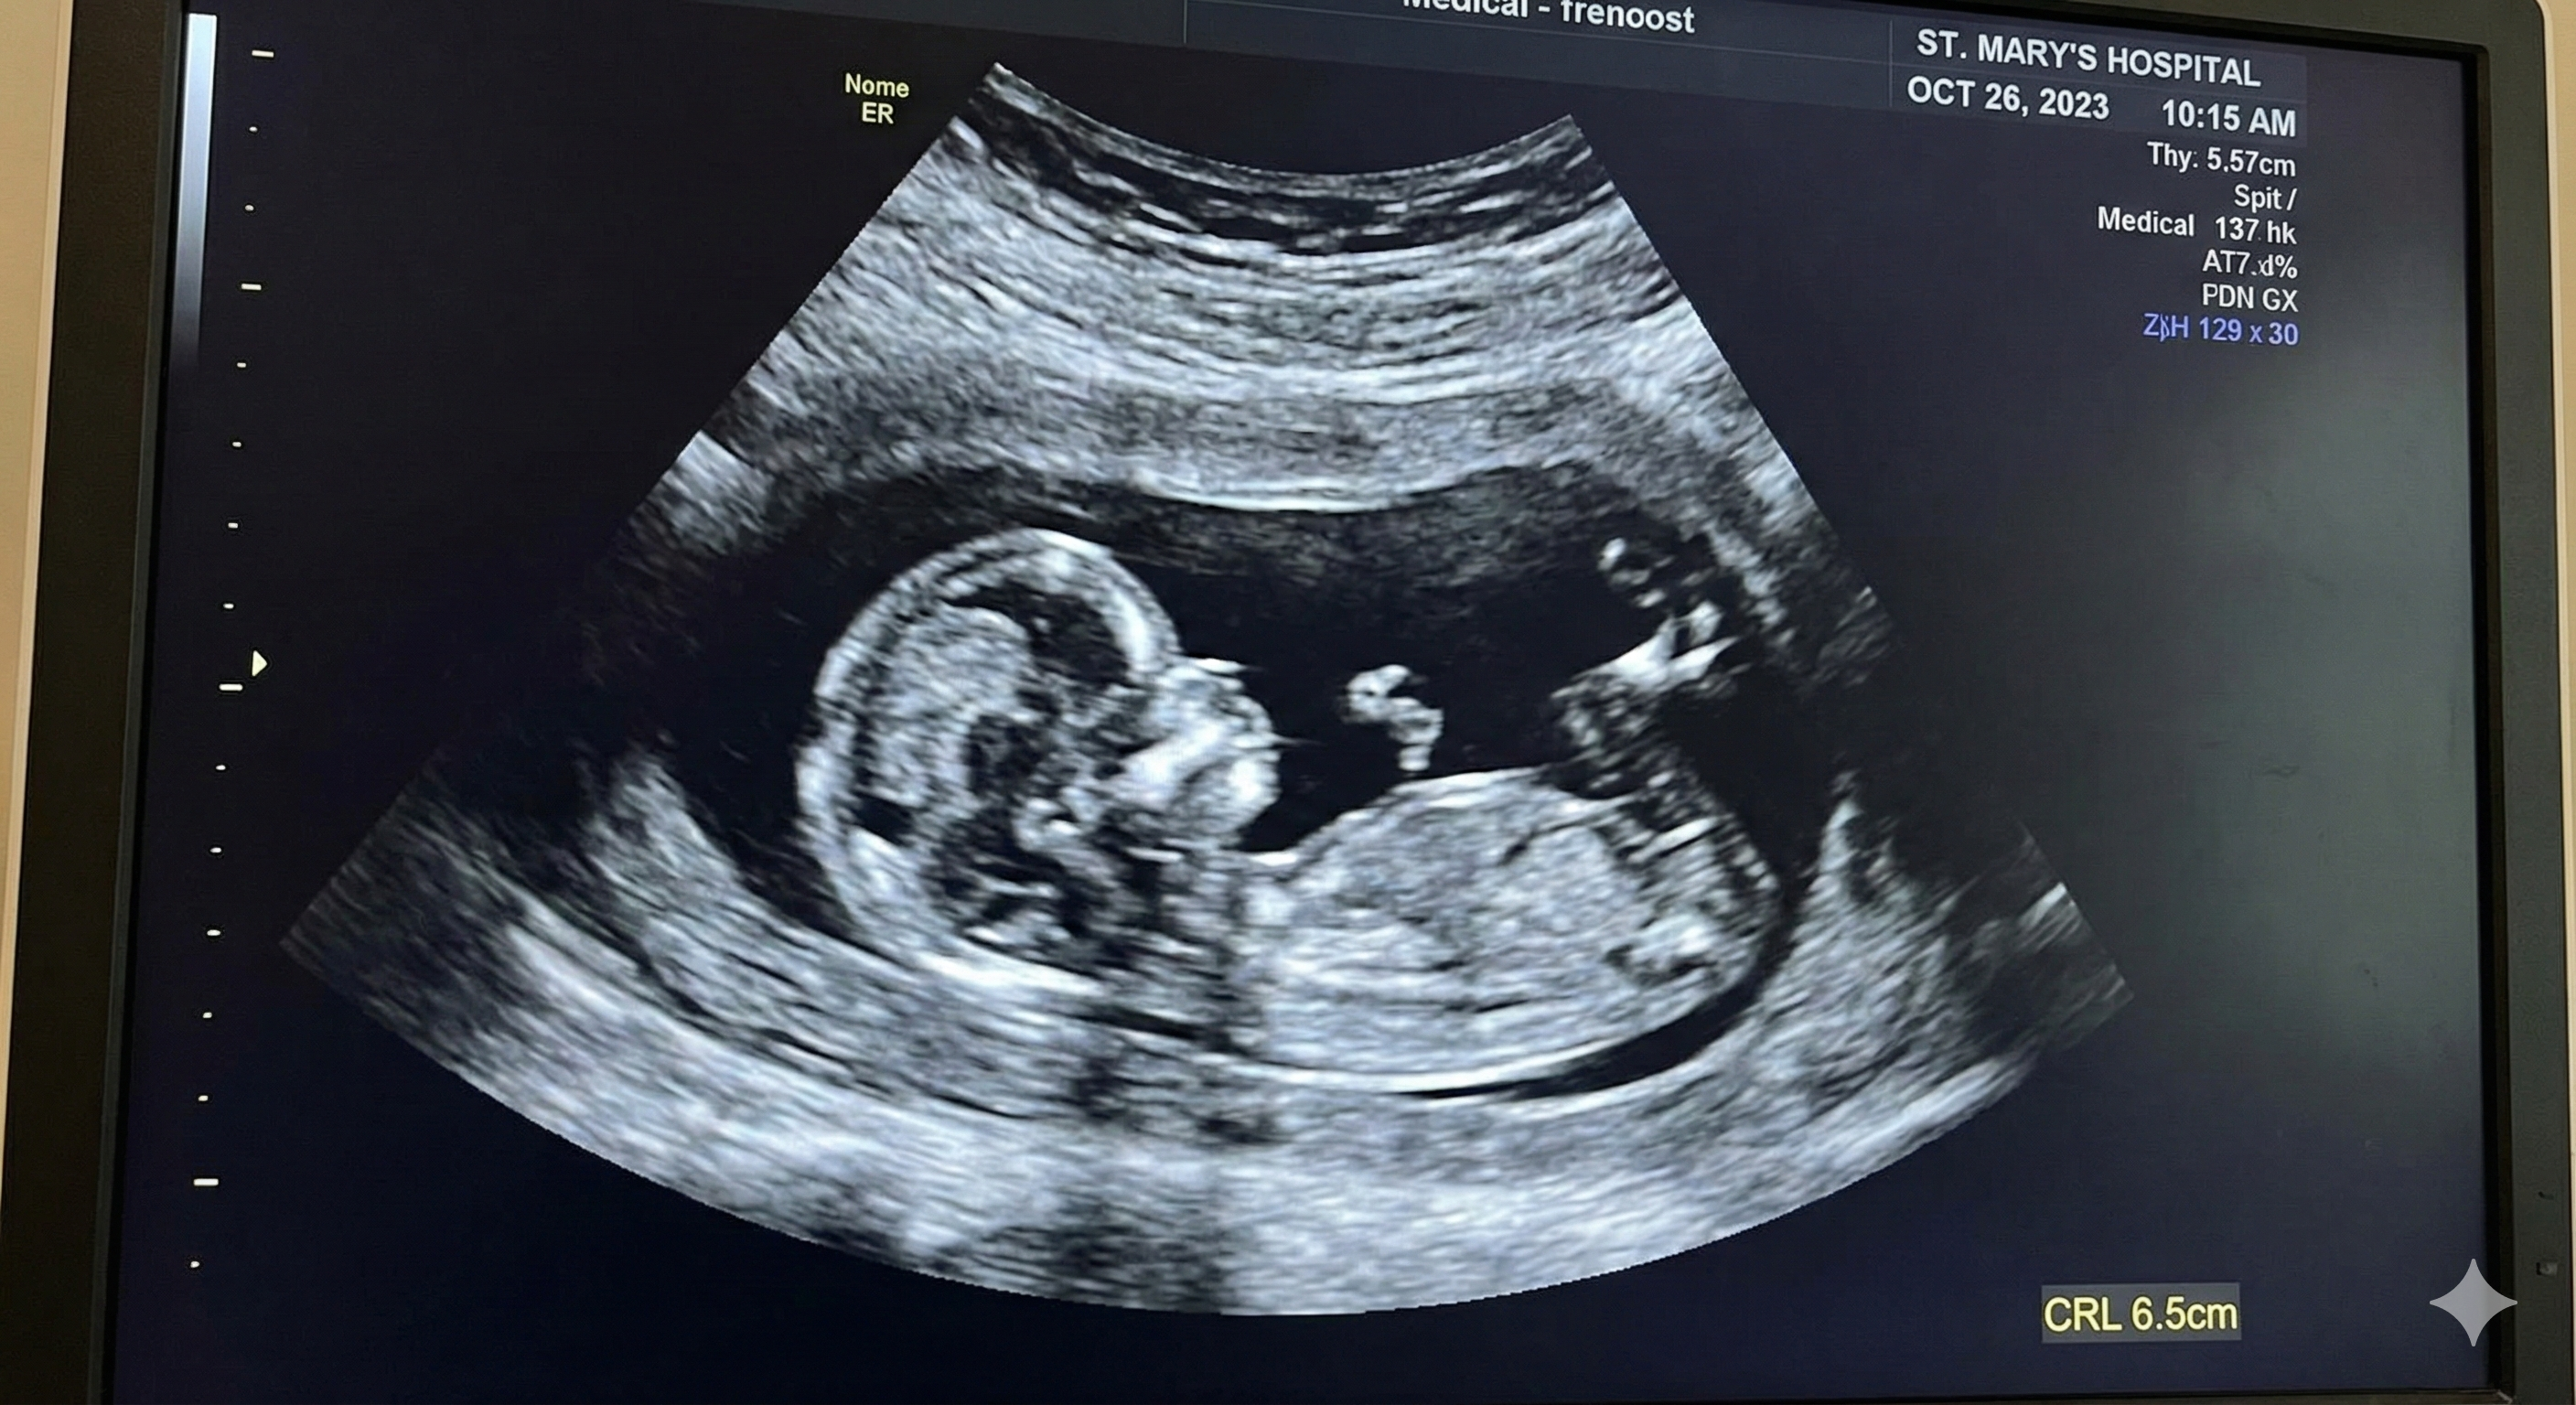

Ultrasound is the most widely used imaging method to view the fetus, and it’s commonly used to assess and monitor health during pregnancy.

Major medical organizations regard ultrasound (and MRI) as safe to the fetus in normal clinical usage.

But again safe doesn’t mean casual. It means medically justified + professionally performed + not unnecessarily prolonged.

The FDA discourages ultrasound used solely for non-medical purposes (like keepsake videos), and says keepsake images are reasonable only if produced during a medically indicated exam without extra exposure.